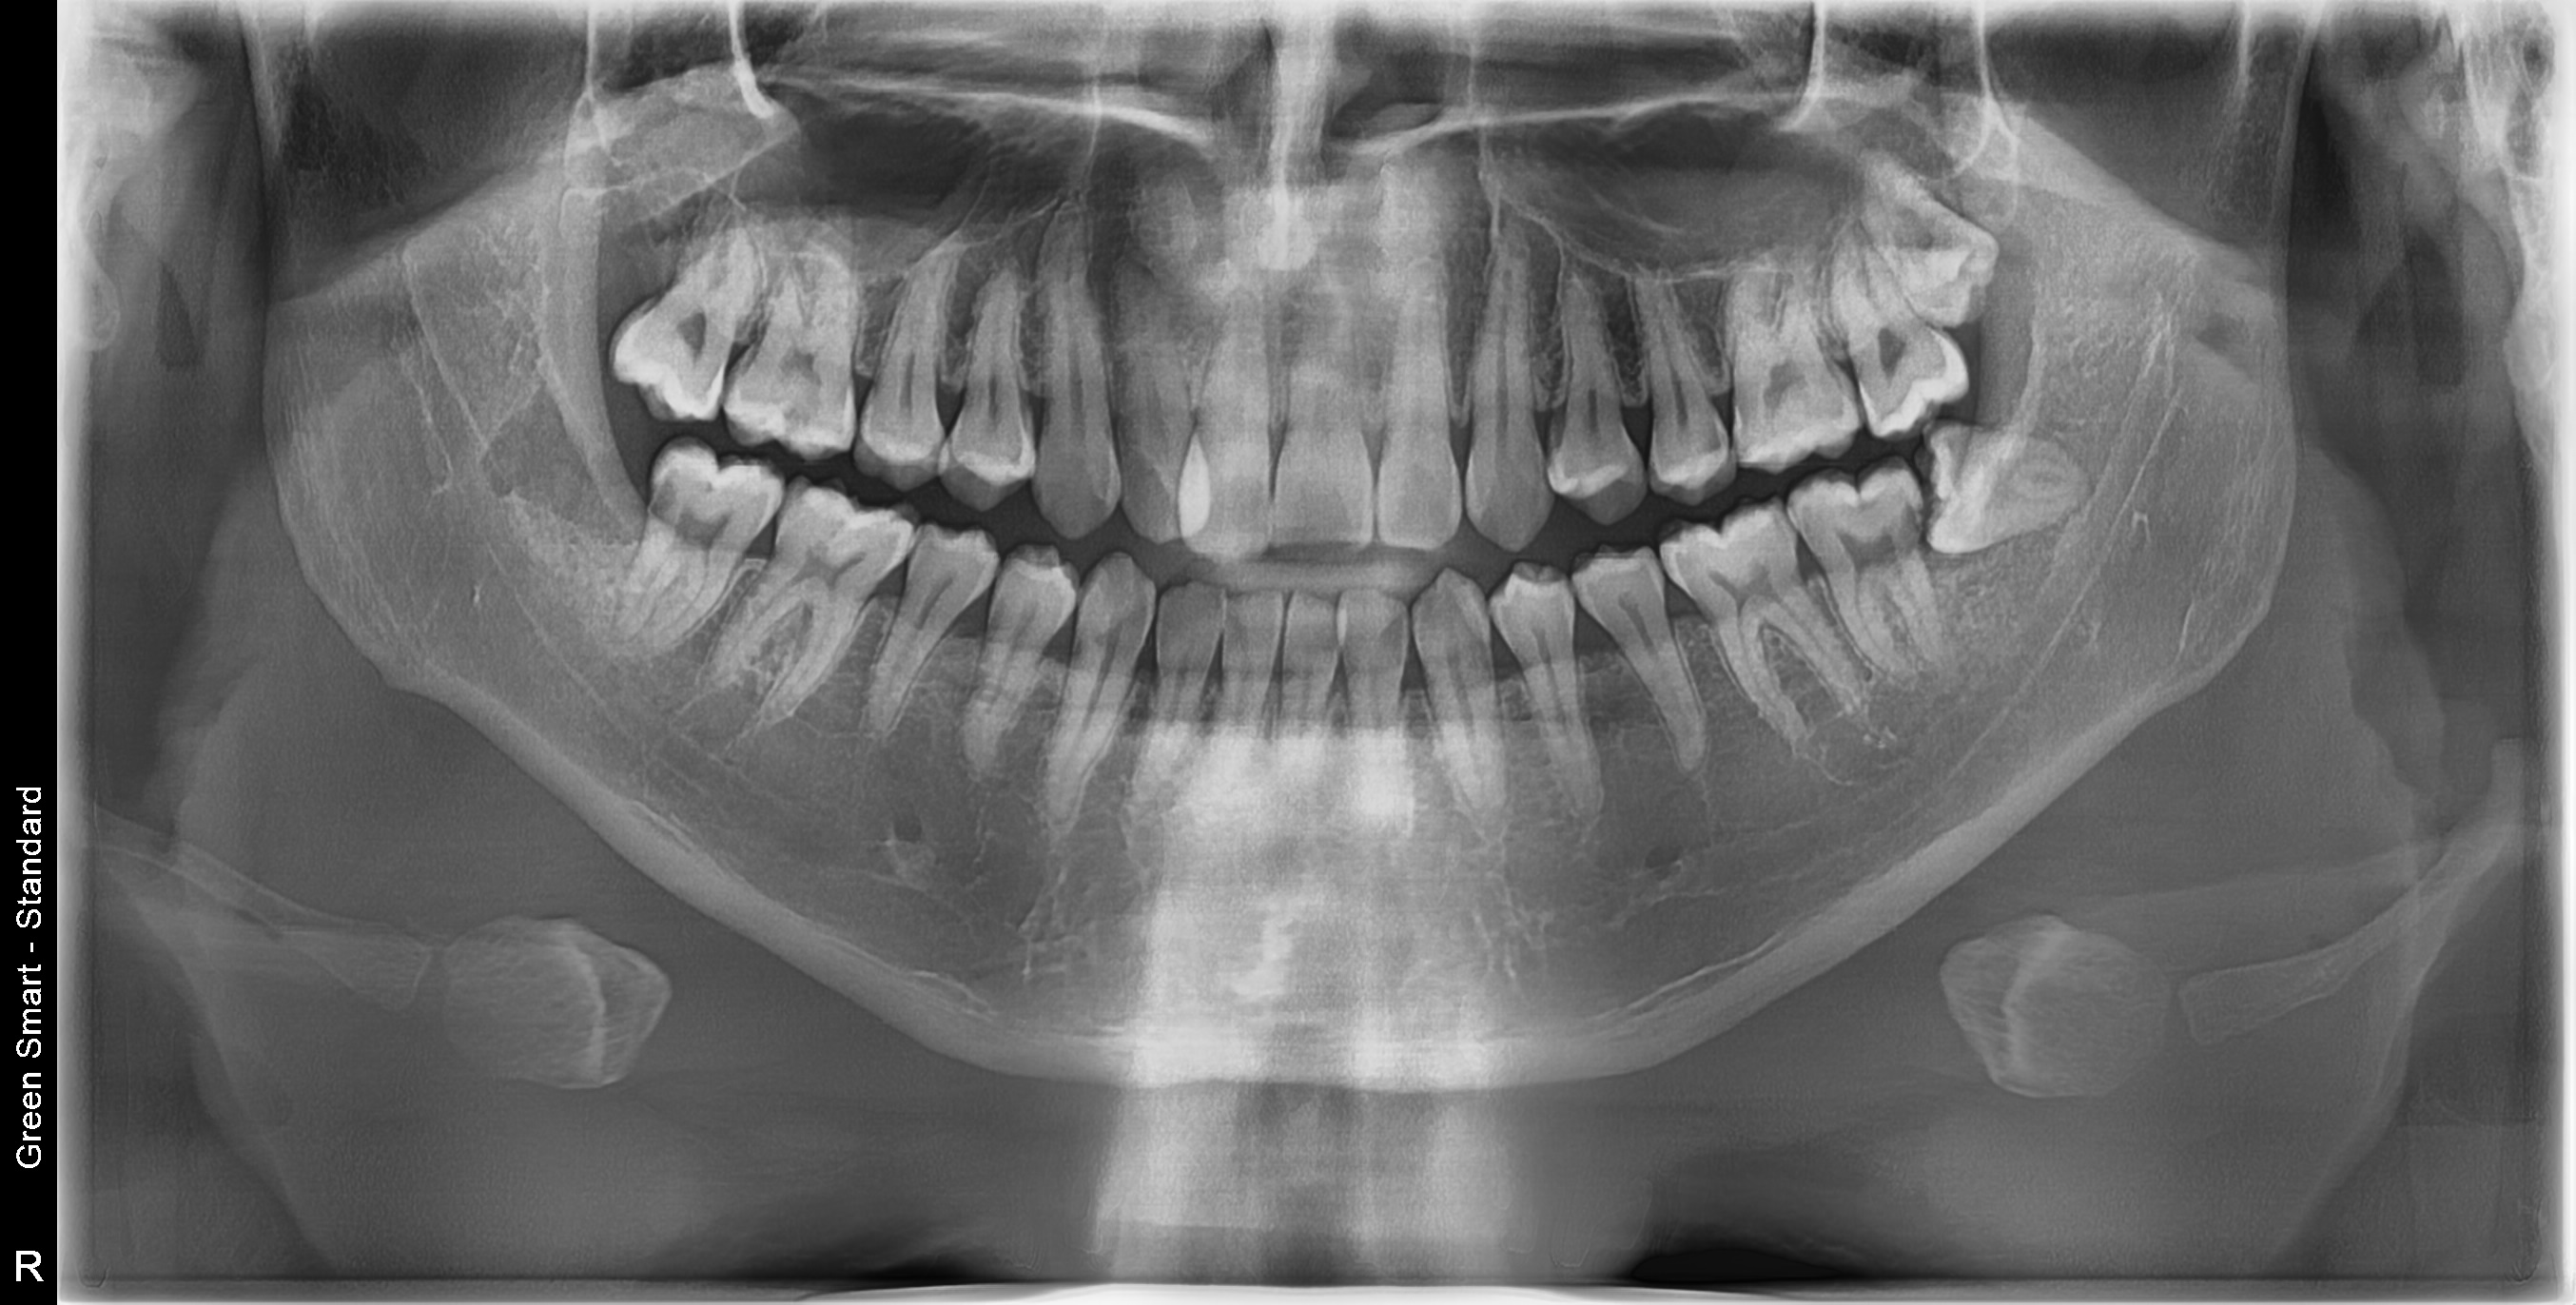

저위험

정상 사랑니

정상적으로 자란 사랑니도 관리가 어려워 충치 위험이 높습니다

고위험

완전매복 사랑니

낭종 형성 가능성이 있어 조기 발치가 필요합니다

치근만곡 사랑니

뿌리가 구부러져 있어 발치 난이도가 높습니다